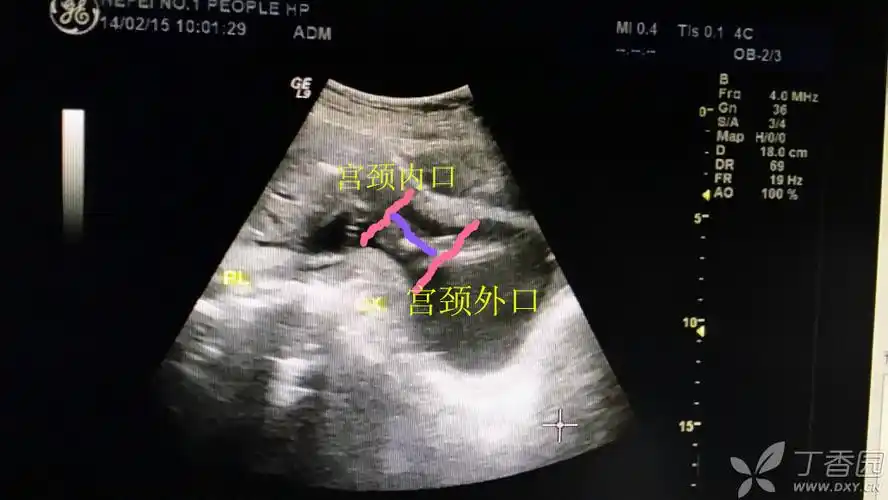

双胞胎宫颈管长度

宫颈管长度短,最终37周 足月出生

我试着帮你测量,紫线应该就是宫颈的长度

医院查了b超和阴超,宫颈内口扩张10mm,宫颈长度31mm,好在堆堆没事.